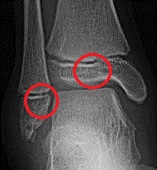

軟骨はX線写真には写りませんので、成長期の足関節をX線撮影すると、骨端線が骨の隙間のように見えます。上記のX線写真でも、骨端線が骨の隙間のように写っています。

オレンジ色の部分は前距腓靭帯です。足首の捻挫に伴って損傷することが多い部位です。

一方、青い丸の部分は、距骨骨軟骨損傷で痛みを感じるところです。

それぞれの場所が近いため、靭帯損傷で痛いと思っていたところ、実は距骨骨軟骨損傷も併発していたということが度々あります。